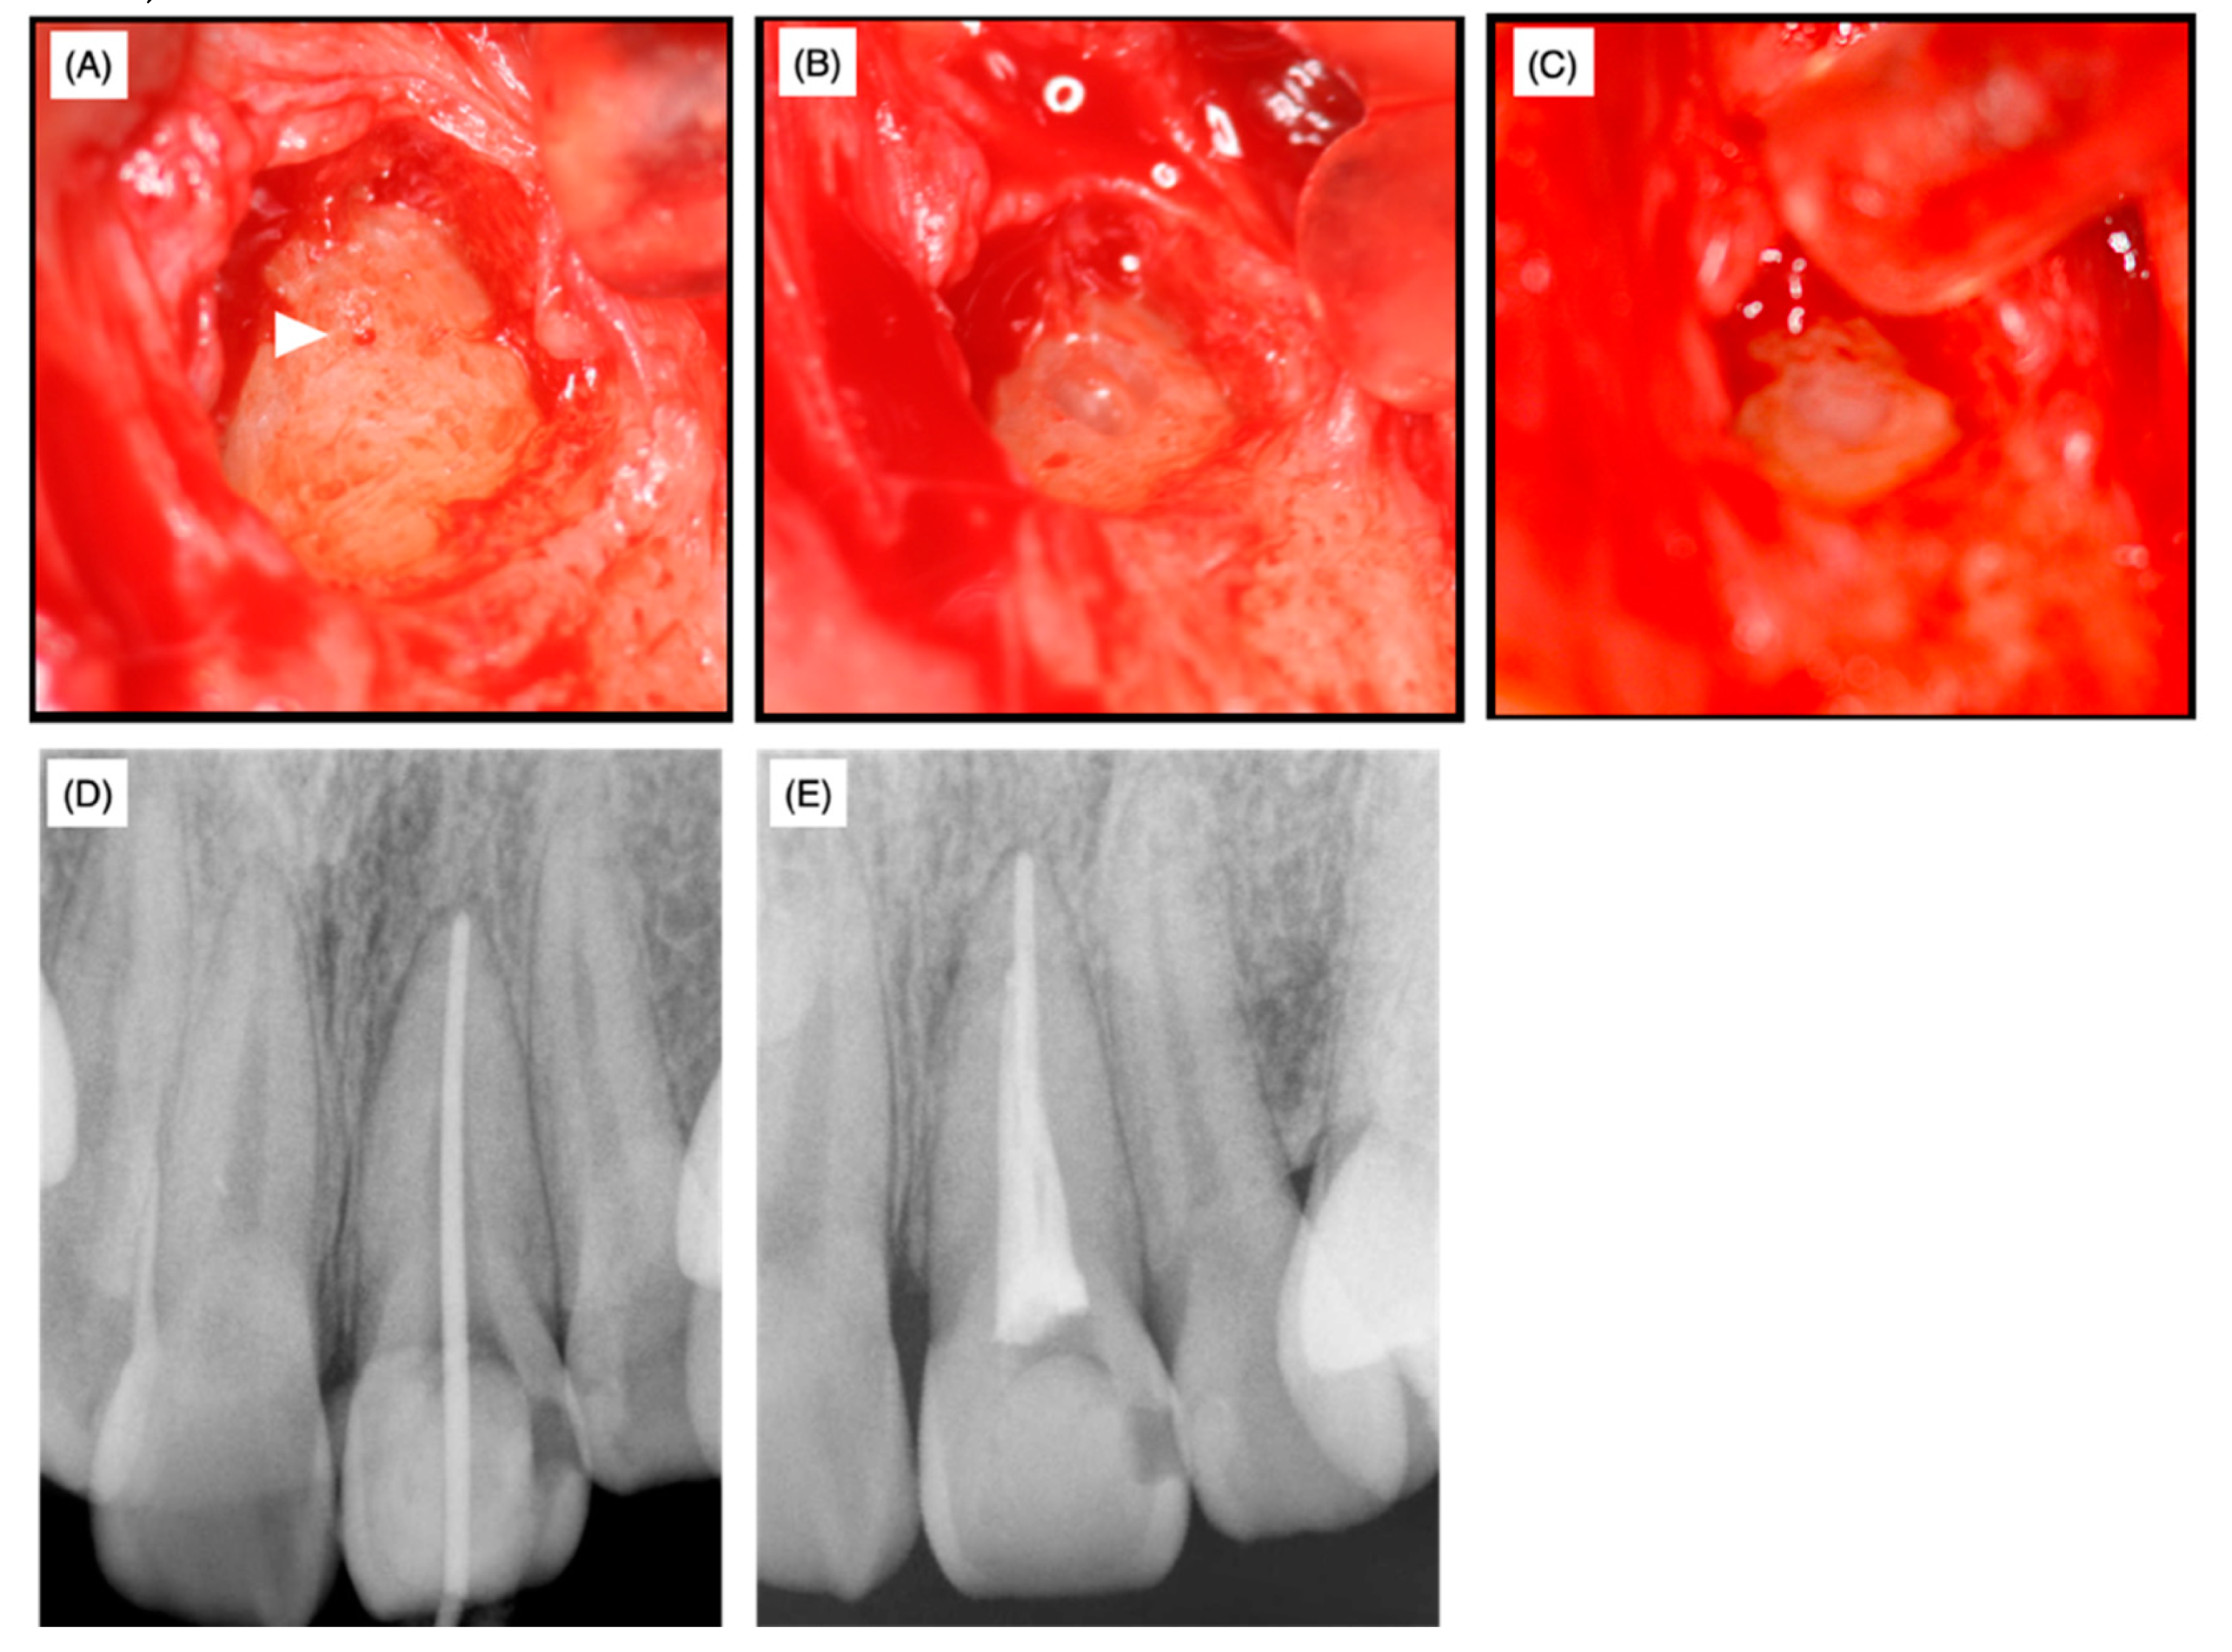

The medical histories of the patient and her family were non-contributory and no traumatic history of the frontal teeth was revealed by history-taking. At the time of the first examination at the university hospital, swelling was observed and the left maxillary incisor was discolored (Figure 2A).

Slight pressure pain and notable fistulization were identified in the swollen area. However, no spontaneous pain or significant perpendicular or horizontal percussion pain was identified. The probing depth of the left maxillary incisor was within 2 mm and tooth movement was within physiological limits; thus, root fracture was not assumed. The palatal side was sealed with hydraulic cement. Dental radiographs taken at the first visit to the university hospital as well as radiographs provided by the private dental clinic revealed that the width of the root canal adjacent to the apex of the left maxillary incisor was narrower than that of the maxillary right central incisor (Figure 1 and Figure 2B). The upper two-thirds of the crown side were filled with Calcipex II® from the previous treatment. Moreover, the width of the periodontal ligament space was slightly enlarged (Figure 1 and Figure 2B).

Figure 2. Preoperative intraoral photograph (A) and dental radiophotograph (B).